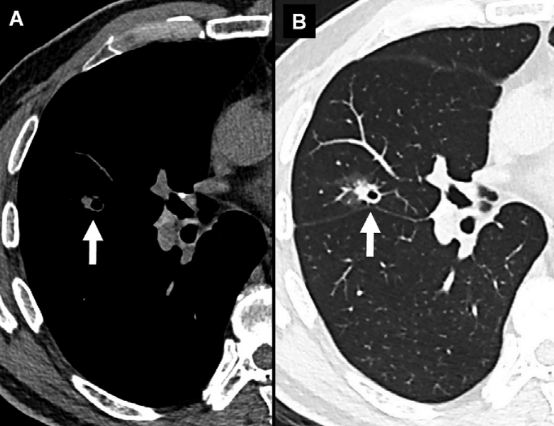

右肺上叶结节 (箭头)。A、纵隔窗图像仅显示结节实体成分的核心。B、肺窗图像可显示结节的整个实性成分、囊性和磨玻璃成分。

纵隔窗会减少亚实性结节磨玻璃成分的显示,因此,所有结节测量应使用肺窗的图像。